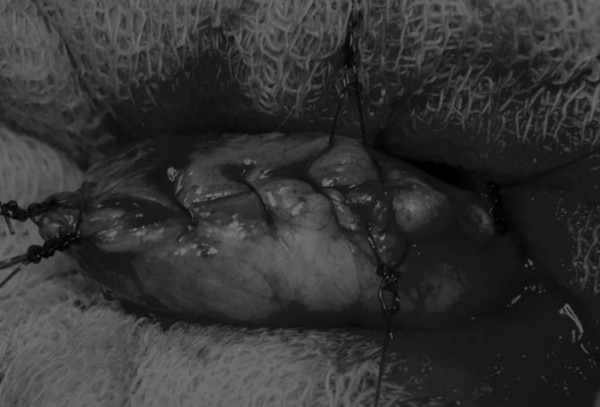

在牵引缝线之间选择血管扩张较差的区域用手术刀切开膀胱壁(图3)。在牵引缝合线之间用手术刀在血管不良的区域做切口。切开膀胱壁后,膀胱内的手术可按手术方案实施,例如取出结石(图4)。

图4 这张图显示了从膀胱中取出的大量结石